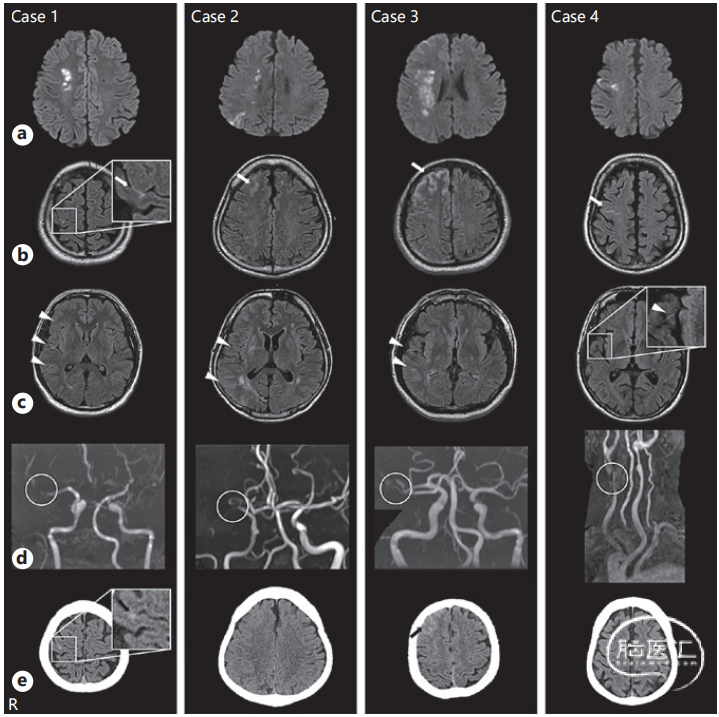

接上面的病例:4例cSAH患者

a. DWI b、c. FLAIR;d. MRA e. CT

Case1,CT时间在MRI即刻

Case2、3,CT时间在MRI后2天

Case4,CT时间在MRI后3天

Case2和4 从头CT上已看不出高密度

小结论:通过这4例病例我们可以看到凸面蛛网膜下腔出血能够很快被吸收。

这篇文章的结论:

凸面型蛛网膜下出血在7天内就可能会消失,这是使用更灵敏的核磁进行判断的结论;如果使用CT判断,可能是信号消失的时间会更早。